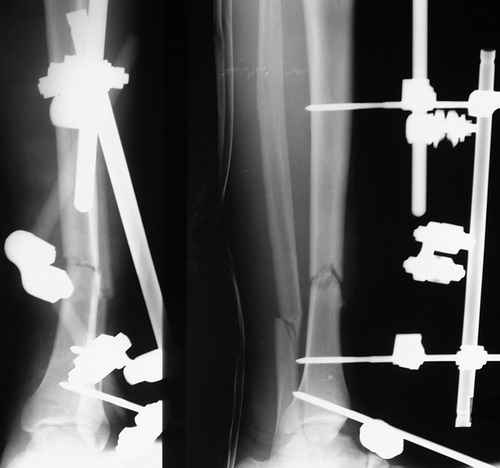

Уважаемые коллеги, спасибо всем за участие. Сегодня просто просмативал старые страницы, да и пациента относительно недавно вспоминали. Случай подошел к логическому завершению:

Итак - удалили стержень, воспалительный процесс к тому моменту купирован, наложили кастовую повязку и в течение 3 месяцев на контрольных рентгенограммах - признаки консолидации. Уже в сентябре, т.е черз 5 месяцев после нагноения пациент вернувшиь с подвождной охоты привез здорового сазана - основная жалоба - ноги побаливают после длительного лпаваня в ластах. Прилагаю снимки через год после удаления стержня. Вот такая, на этот раз счастливая казуистика.